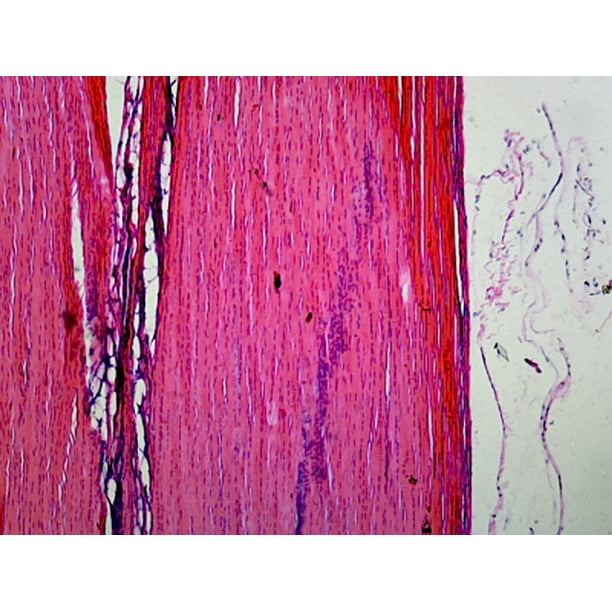

Tendon Junction Mammalian Longitudinal Section HE Stain Biology Diagrams sipates stress at the junction between the relatively soft tendon and the hard bone and thereby reduces peak stress. The myo-tendinous junction is a highly specialised region where collagen ๏ฌbrils are inserted deep into recesses formed by myocytes. This arrangement allows transmission of tension forces across the tendon and muscle interface.1 The musculotendinous junction is the point where the muscle pierces the tendon. The osteotendinous junction is the point where the tendon inserts on the bone. Cell Population and the Extracellular Matrix. Tenocytes and tenoblasts are specialized fibroblasts that coexist in tendinous tissue. Tenocytes are elongated, while tenoblasts are ovoid.

The muscle-tendon junction (MTJ) is a highly specific tissue interface where the muscle's fascia intersects with the extracellular matrix of the tendon. The MTJ functions as the particular structure facilitating the transmission of force from contractive muscle fibers to the skeletal system, enabling movement. Considering that the MTJ is continuously exposed to constant mechanical forces The myotendinous junction (MTJ) is a specialized structure in the musculotendinous system, where force is transmitted from muscle to tendon. Animal models have shown that the MTJ takes form of tendon finger-like processes merging with muscle tissue. The human MTJ is largely unknown and has never been described in three dimensions (3D). Musculotendinous junction (MTJ): The point where the tendon attaches to your muscle. Note this is a frequent site of injury. Osteotendinous junction (OTJ): The point where the tendon attaches to your bone. The Sharpey fibers that are part of the tendon extend into the bone.

Tendinous portion. The tendinous portion is made up of multidirectional collagen fibres. but rather in the body of the muscle cells just proximal to the MTJ. Hjort M, Hansen KK, Qvortrup K, Kjaer M, Krogsgaard MR. The human myotendinous junction: an ultrastructural and 3D analysis study. Scand J Med Sci Sports. 2015 Feb;25(1):e116-23 Myotendinous junction (MTJ) is a part of the myotendinous unit. The myotendinous unit consists usually of bone, enthesis, tendon, myotendinous junction and muscle, and is responsible for producing skeletal movement.. The MTJ has a distinctive form with the muscle membrane having many infolds which the collagen fibrils from the tendon join with (see image 1) . Connexin 43 is situated in gap junctions between cells in rows along the collagen fibres. Connexins 26 and 32 have a more diffuse pattern. Each tendon will differ throughout the body depending on the rate in which they are strained. The behaviour of the collagen within the tendon depends on the intramolecular types, quantity and bond.